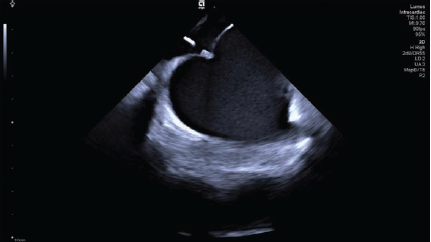

The catheter-based treatment known as pulsed-field ablation (PFA) is emerging as an innovative method of ablation for the treatment of atrial fibrillation. It creates precisely demarcated cardiac lesions that preserve tissue architecture; cell death is confirmed by histological evidence of electroporation, which uses electrical fields to increase cell permeability. PFA can be augmented via four-dimensional (4D) intracardiac echocardiography (ICE) to guide catheter placement, verify tissue contact, and evaluate lesion formation. Additionally, 4D ICE may help clinicians assess sufficient energy delivery to intended tissue and minimize the potential for hemolysis, or the rupturing of red blood cells. In this case, 4D ICE (AcuNav Lumos 4D ICE catheter, Siemens Healthineers) was used to perform PFA and provided detailed views of cardiac anatomy and visualization of tissue contact in multiple planes (Figures 1-2). AcuNav Lumos 4D ICE also guided the transseptal puncture and tenting with visualization of left atrial appendage in the far field (Figure 3) to confirm absence of thrombus.